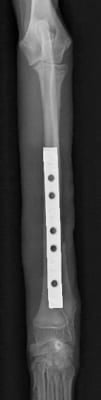

右前肢

左前肢

*写真なので写りこみをカットしています。

橈骨・尺骨ともに癒合してますし、

橈骨の髄腔もきちんと確認できます。

極端な骨硬化像も認めないので経過観察終了としました。